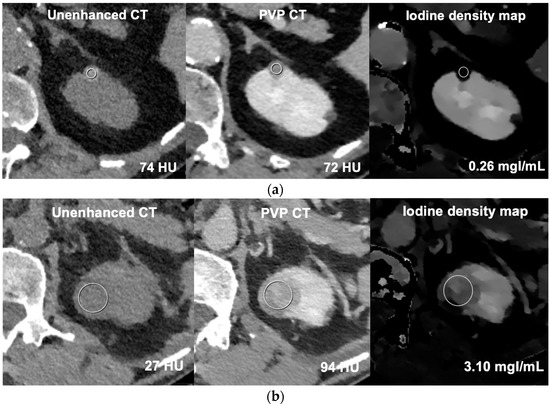

| ΔHU on multiphase CT, median (Q1–Q3; range) | 0 (−3–4; −18–18) | 57.5 (34–82; 22–142) | 1 (−2–7; −13–18) | 59 (34–84; 22–142) |

| Iodine concentration (mgI/mL), median (Q1–Q3; range) | 0.39 (0.25–0.58; 0.00–1.66) | 2.55 (1.73–3.57; 0.80–5.95) | 0.45 (0.26–0.74; 0.02–1.66) | 2.74 (1.78–3.59; 0.80–5.95 |